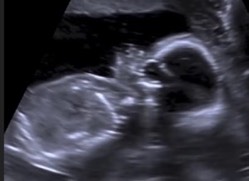

Wyoming legislators voted to ensure women see an ultrasound of their baby before taking chemical abortion drugs. The state's socially liberal governor vetoed it, but legislators overrode his veto.

(Cheyenne, Wyoming) — [LifeSiteNews.com] Wyoming legislators overrode the veto of the state's socially liberal governor to pass a law requiring women to have an ultrasound before obtaining chemical abortion drugs. (Screengrab image)

While abortion drugs can never truly be safe, since they intend to kill a preborn baby, an ultrasound can detect an ectopic pregnancy. Abortion drugs cannot be used when a woman has an ectopic pregnancy.

The bill also requires the abortionist to give women information about their unborn baby and to show them the baby's heartbeat.